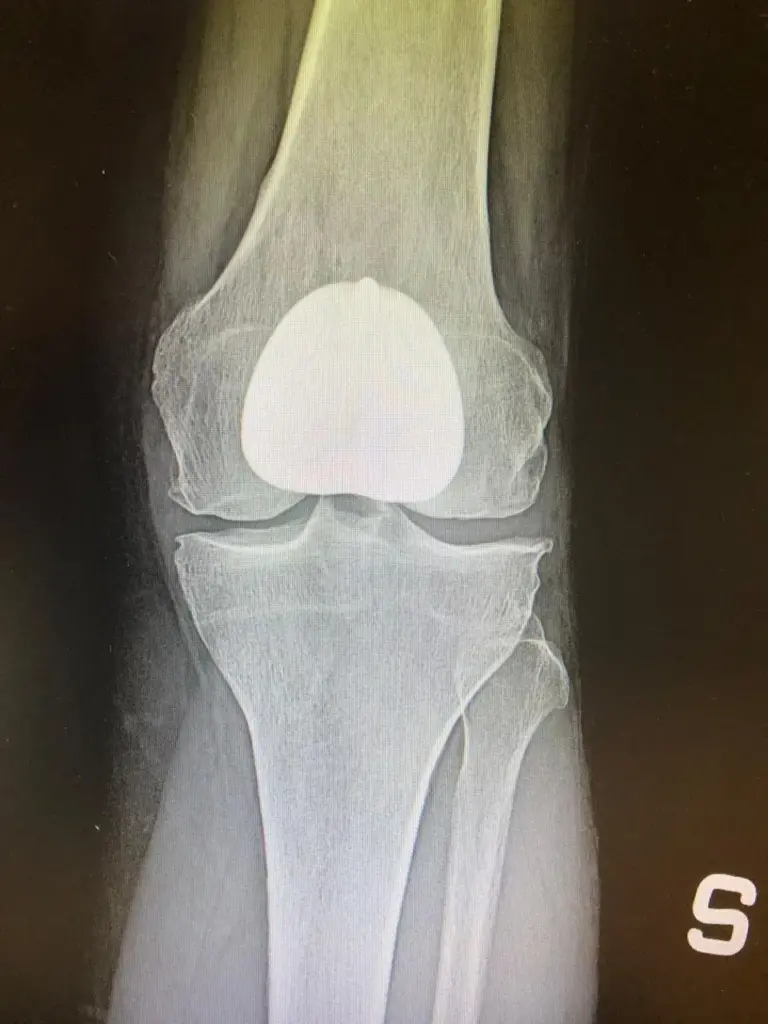

[vc_row rt_row_background_width=”fullwidth” rt_row_content_width=”default” rt_row_style=”default-style” rt_row_borders=”” rt_row_shadows=”” rt_row_paddings=”true” rt_bg_effect=”classic” rt_bg_image_repeat=”repeat” rt_bg_size=”cover” rt_bg_position=”right top” rt_bg_attachment=”scroll” rt_bg_video_format=”self-hosted”][vc_column rt_column_shadow=”” rt_bg_image_repeat=”repeat” rt_bg_size=”auto auto” rt_bg_attachment=”scroll”][vc_column_text]Patologia che riguarda un over 60 su 3, l’artrosi del ginocchio, conosciuta anche come gonartrosi, si contraddistingue per la degenerazione della cartilagine che riveste il femore e la tibia. In alcuni casi, può essere coinvolta anche quella della rotula.

Nei casi in cui l’artrosi al ginocchio è talmente avanzata da compromettere la qualità della vita del soggetto che ne soffre (i principali campanelli d’allarme in questo caso sono il dolore e la limitazione funzionale), la soluzione da adottare è il ricorso alla chirurgia protesica. Quest’ultima, per rispondere a un’esigenza sempre più forte soprattutto dal punto di vista numerico (negli ultimi decenni l’incidenza è aumentata notevolmente e il problema riguarda spesso anche persone di età inferiore ai 60 anni), è stata interessata da innovazioni rilevanti, come per esempio la realizzazione di impianti protesici customizzati. Nelle prossime righe, parlerò meglio del workflow che permette di crearli e soprattutto dei vantaggi che comporta il loro utilizzo.

Il processo di realizzazione delle protesi di ginocchio customizzate parte dall’esecuzione di una TAC, indagine che consente di avere a disposizione una ricostruzione tridimensionale del ginocchio del paziente.

I risultati della TAC vengono infatti sottoposti all’elaborazione da parte di un software, che restituisce dati utili innanzitutto alla creazione delle maschere PSI (Patient Specific Instrument), modelli che permettono di ottimizzare il posizionamento della componente protesica, che viene realizzata rispettando l’allineamento cinematico.[/vc_column_text][/vc_column][/vc_row][vc_row rt_row_background_width=”fullwidth” rt_row_content_width=”default” rt_row_style=”default-style” rt_row_borders=”” rt_row_shadows=”” rt_row_paddings=”true” rt_bg_effect=”classic” rt_bg_image_repeat=”repeat” rt_bg_size=”cover” rt_bg_position=”right top” rt_bg_attachment=”scroll” rt_bg_video_format=”self-hosted”][vc_column rt_column_shadow=”” rt_bg_image_repeat=”repeat” rt_bg_size=”auto auto” rt_bg_attachment=”scroll”][vc_column_text]